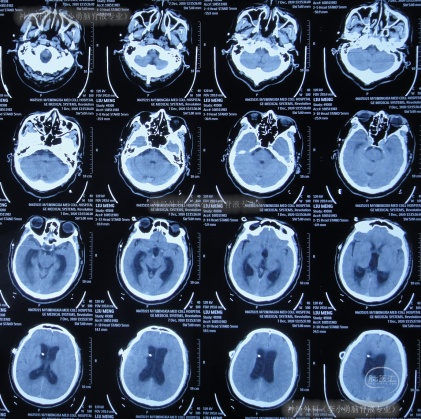

但出院后1个月即2020年12月6日(脑室腹腔分流术后3年零2月),再次出现嗜睡,第3次就诊该院,查头颅CT(片子丢失)后认为脑室系统与1月前相比并未明显扩张,但第2天即2020年12月7日,出现昏迷,大小便失禁,再查头颅CT(图-3)后认为脑室有大。

图-3:2020年12月7日头颅CT